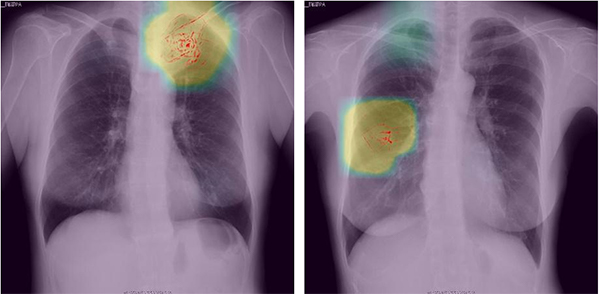

深層学習を活用した画像解析で異常陰影を検知した場合のイメージ (開発中の画面で,実際に使用されるものとは異なる場合がある)

今回PFNが開発した診断補助ツールは,PFN独自の深層学習アルゴリズムを用い,実際の胸部X線画像による肺がんの診断データを多量に事前学習したモデルを使用する。検診者の画像をこのモデルで解析し,肺がんの可能性がある異常を検知した場合は画面上に対象部位を表示し,読影医の診断を支援する。従来の読影医2名による体制に変わりはなく,本ツールを用いて医師が最終的に診断する。検診の対象となるデータには,医療情報を匿名化して安全に保管・利用できるNOBORIのクラウドサービス「NOBORI」を使用する。